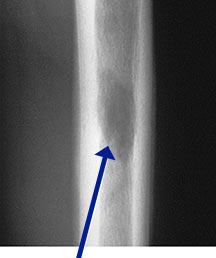

- May arise from any bone and any site within a bone (epiphyseal, metaphyseal, diaphyseal)

- Radiographically variable appearance: may appear benign (geographic) or malignant (permeative or moth eaten)